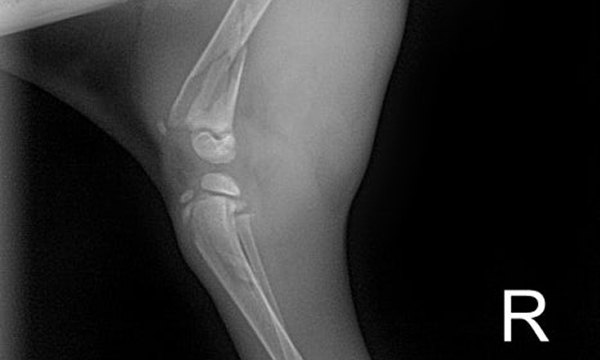

수술케이스 ④ 블*강아지 - 경골 복합골절

수술케이스 4 before BEFORE

수술케이스 4 after AFTER